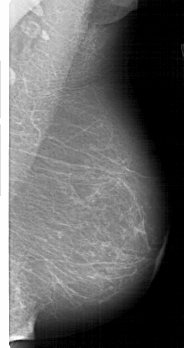

A_1812_1.LEFT_MLO

LEFT_MLO LINES 5206 PIXELS_PER_LINE 2821 BITS_PER_PIXEL 12 RESOLUTION 43.5 OVERLAY